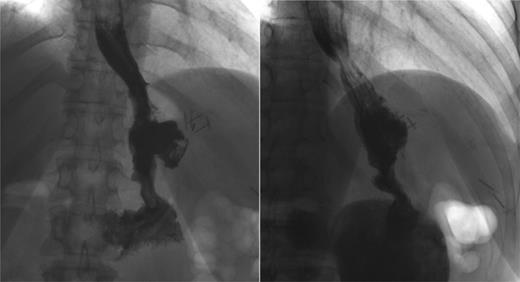

An outpatient OGD, with the intent to close the fistula, was carried out; the tract was defined after injection of contrast and stabilized with two clips (Fig. 1).

Endoscopic attempt to close the fistula. Oesophago-gastro-duodenoscopy sequence that shows the opening point of the fistula (arrow) and its stabilization with clips.